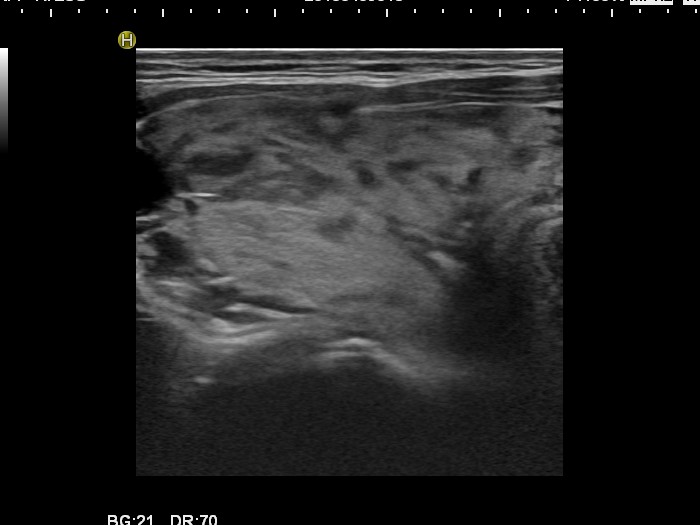

Graves' disease - Case 1049

Follow-up investigation 30 months after first visit (ultrasonographic picture 1)

Patient one year after discontinuation of thyrostatics in hyperthyroid state

Right lobe, transverse scan. The echogenicity index is around 20%.